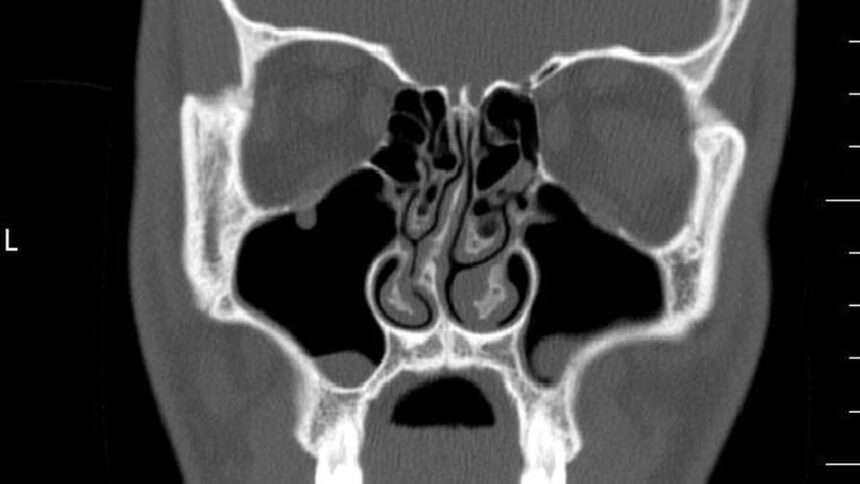

For analysis, medical testing stays commonplace. “The take a look at alone will diagnose the bend and you may see extra with an endoscopic or CT scan,” stated Shruthi Sreekumar of Affiliate Advisor at Rela Hospital in Chennai. In some circumstances, CT scans of the sinuses may also help to establish associated ailments.